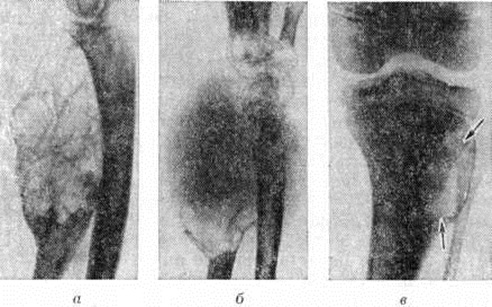

Рис. 1.

Микропрепарат остеобластокластомы: 1 — гигантские многоядерные клетки; 2 — остеобластические клетки; окраска гематоксилин-эозином; × 120.

Микроскопически Остеобластокластома построена из клеточных элементов двух типов: преобладают слегка вытянутые мелкие клетки с округлым или овальным ядром, среди которых более или менее равномерно распределены многоядерные гигантские клетки, содержащие иногда до 50—100 ядер (рисунок 1), практически не отличающихся от ядер мелких клеток. В одноядерных клетках встречаются митозы, в многоядерных — фигуры деления отсутствуют. Наряду с этими двумя видами клеток в Остеобластокластома встречаются фибробласты, поля ксантомных клеток, участки кровоизлияний с макрофагальной реакцией. В центральных отделах Остеобластокластома отмечается своеобразный бессосудистый тканевой кровоток — кровь циркулирует непосредственно между клетками, образуя местами небольшие скопления, как бы «заболачивая», по выражению А. В. Русакова, ткань опухоли и приводя к образованию кист. Это даёт основание некоторым исследователям говорить о возможности исхода Остеобластокластома в костную кисту (смотри полный свод знаний). Значительное число кровеносных сосудов выявляется преимущественно по периферии новообразования. При интенсивном росте опухоли многоядерные гигантские клетки утрачивают чёткость контуров, число ядер в них увеличивается. При медленном росте многоядерные гигантские клетки уменьшены в размерах, округлой формы с чёткими контурами, содержат небольшое количество ядер. В ряде случаев на первый план выступают явления фиброза. При этом многоядерные клетки ещё больше уменьшаются в размерах, имеют неровные зазубренные очертания, содержат значительно меньше ядер, цитоплазма их становится плотной, базофильной. При исходе Остеобластокластома в кисту опухолевая ткань иногда почти полностью редуцируется.